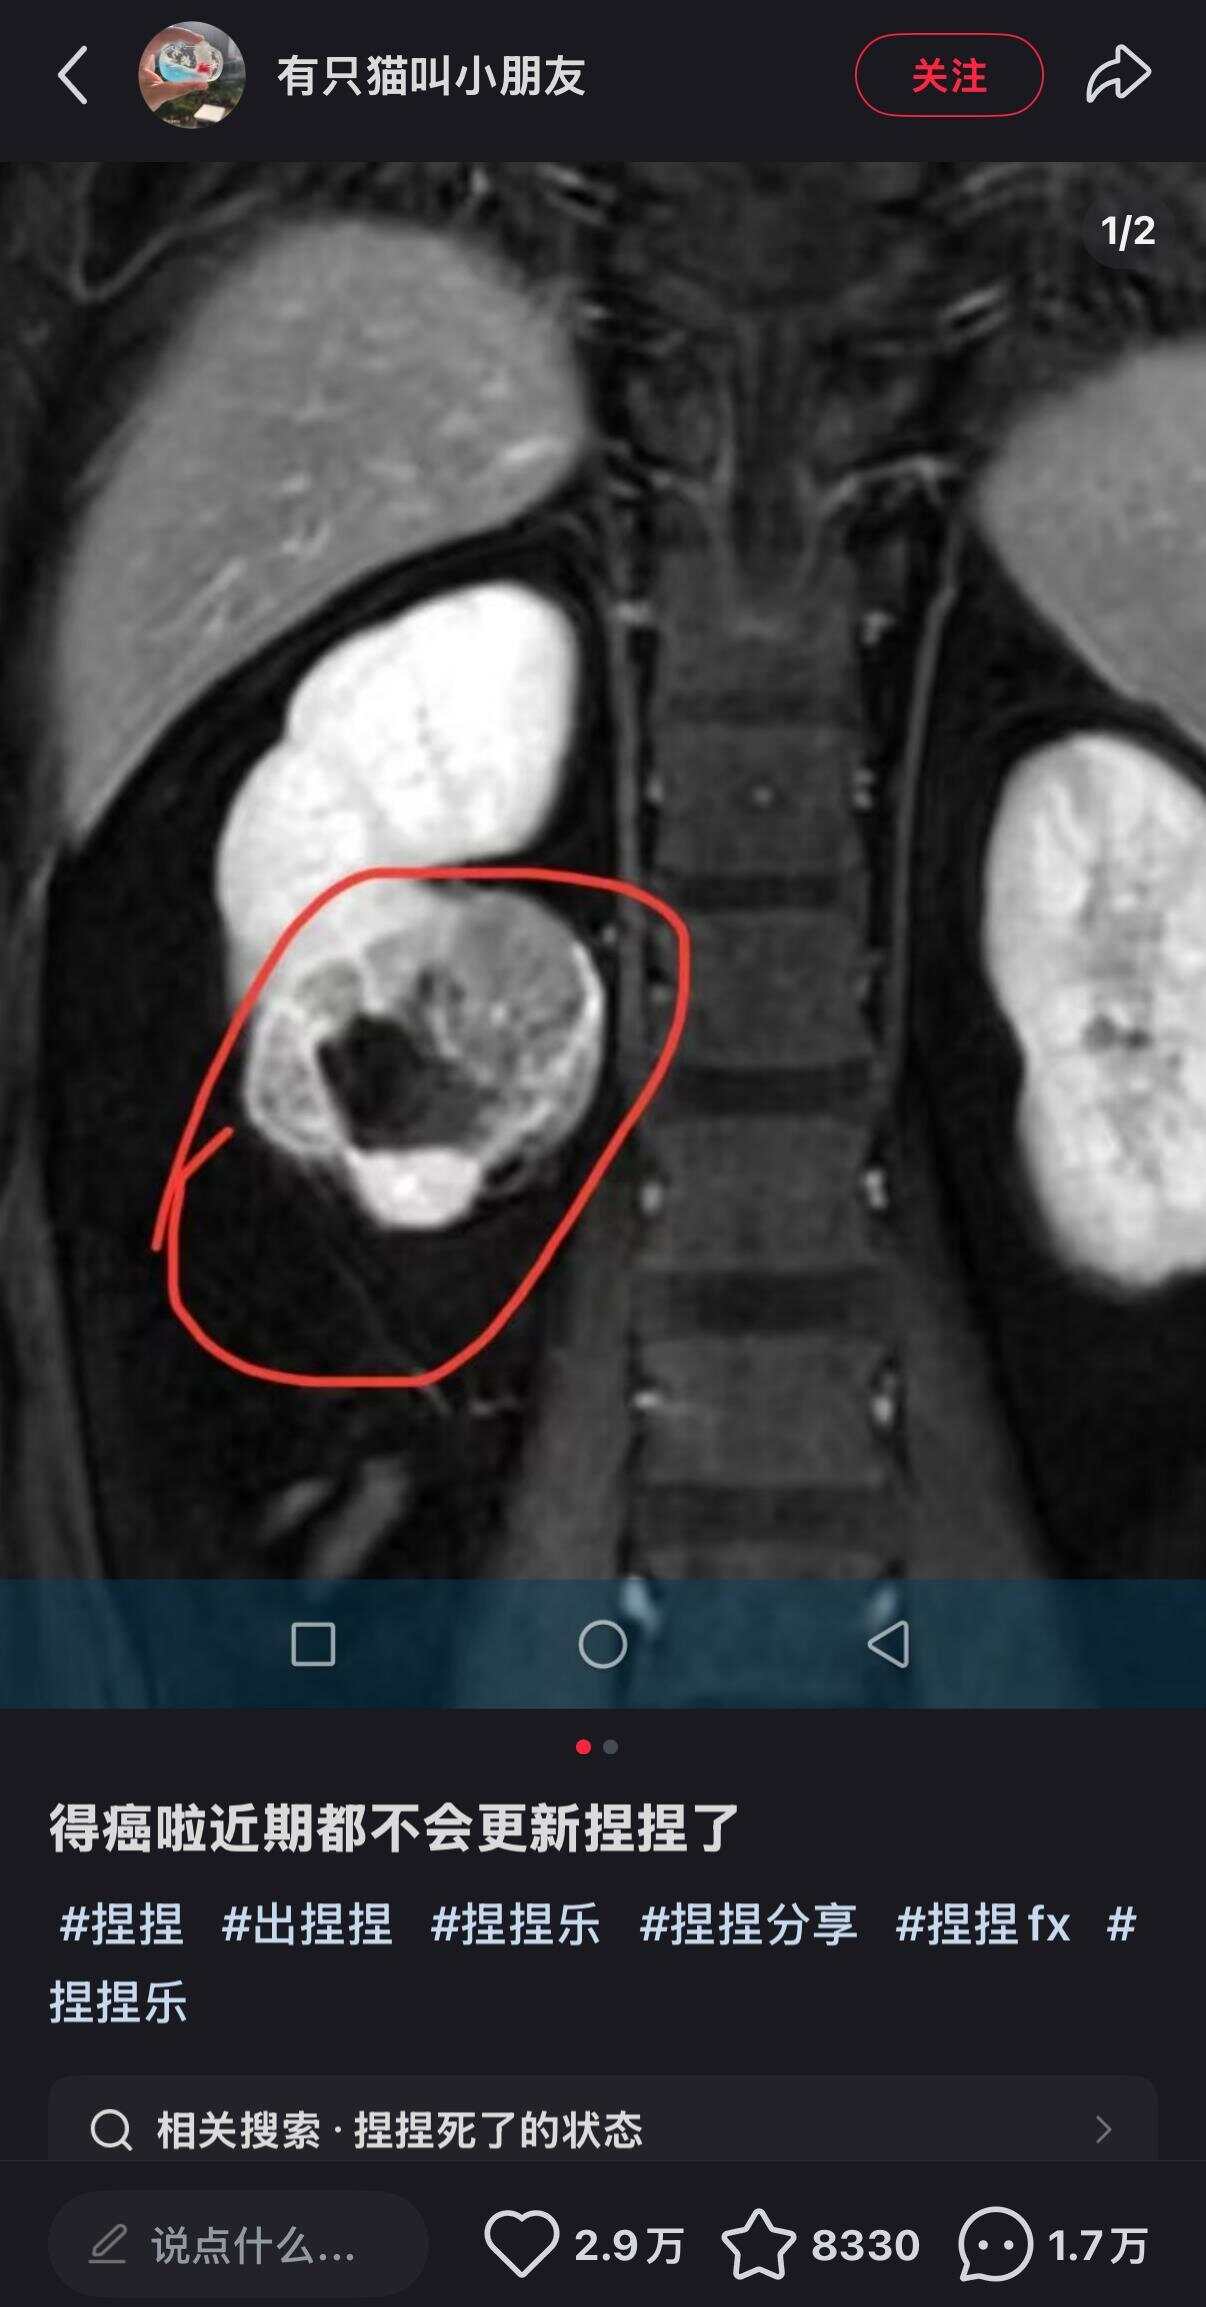

0316-5789130近日,解压玩具博主“有只猫叫小朋友”在社交平台宣布罹患癌症并暂停更新视频。虽然未透露其患病原因,但有网友猜测,是否与其常揉捏“捏捏”玩具有关。由此,也引发了公众对“捏捏”玩具安全性的担忧。